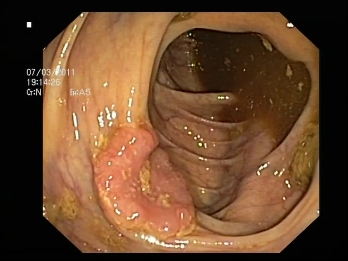

COLONOSCOPIA: Es la exploración fundamental para el diagnóstico ( ver más información aquí)

Es la degeneración maligna de un pólipo o un tumor de colon.

El cáncer de colon consiste en la aparición de una tumoración vegetante o infiltrativa en la cara interna del tubo digestivo. Esta tumoración tiene tendencia a crecer y diseminarse paso a paso a través de los conductos linfáticos (ganglios), o bien a distancia vía sanguínea (metástasis).